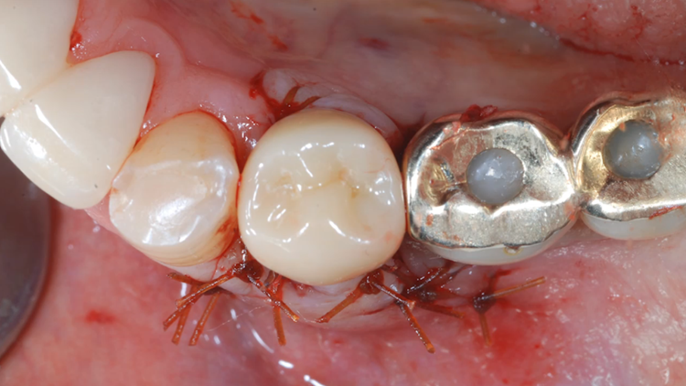

Clinical case: EImmediate implant placement & loading of #35 extraction socket with defect

- Courtesy of Dr. Kwang Bum Park, Korea -

Keywords

Dr. Kwang Bum Park, immediate loading, digital guided surgery, digital ONE-DAY implant, maxillary anterior, #21, guided surgery, immediate loading, AnyRidge, R2GATE, Mega ISQ, MEG Torq, R2GATE Full Surgical Kit

Products:

implant system, R2GATE Guide, R2GATE surgical kit (AnyRidge), Mega ISQ, Mega-Oss

“ One implant /One tooth/ One hour step-by-step

+ associated connective graft ”